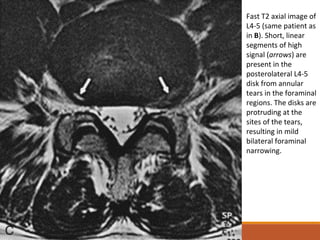

Fast T2 axial image of

L4-5 (same patient as

in B). Short, linear

segments of high

signal (arrows) are

present in the

posterolateral L4-5

disk from annular

tears in the foraminal

regions. The disks are

protruding at the

sites of the tears,

resulting in mild

bilateral foraminal

narrowing.